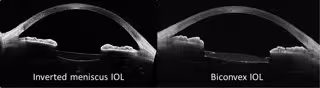

Imagen de las lentes intraoculares

Imagen de las lentes intraoculares - UMU

Estas lentes fueron diseñadas en forma de menisco invertido para mejorar la calidad visual periférica y con una superficie asférica para incitar las distintas profundidades del foco. Esta combinación permitió a la mayoría de los pacientes tener una visión nítida a todas las distancias sin llevar gafas y sin efectos lumínicos adversos, típicos de las lentes multifocales.